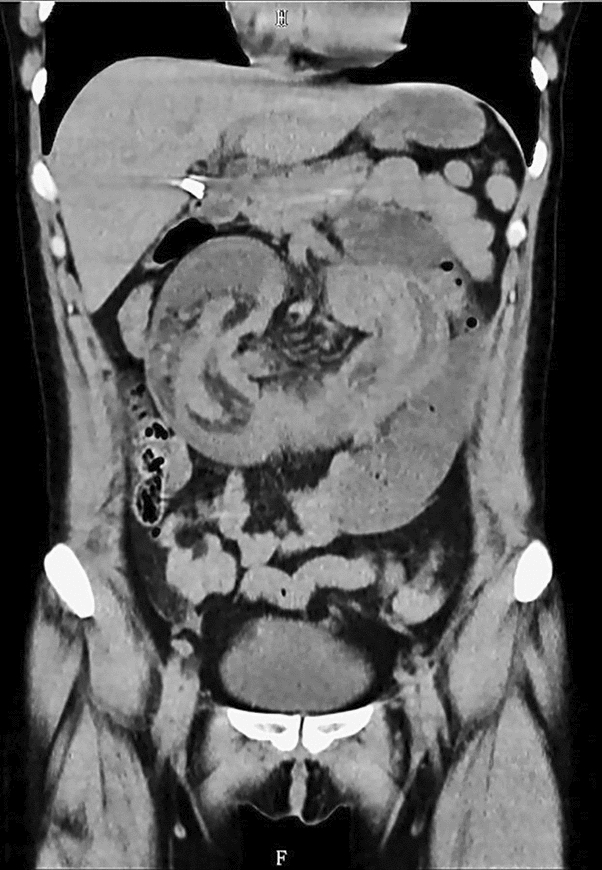

M. Carolina Jimenez, MD; Robert F. Cubas, MD; Jose M. Martinez, MD; University of Miami/Jackson Health System

Introduction: Biologic mesh has been used in clean-contaminated and contaminated fields and while wound infection rates may be high, infection is usually superficial and graft removal is unusual. Biologic mesh has been reported to have higher recurrence rates and poor incorporation into native tissue in comparison to synthetic mesh. Currently, there is no consensus on mesh preservation treatment in cases of mesh infection after hernia repair.

Methods: We present a 72-year-old male with prior radical cystectomy and neobladder creation complicated at the time by neobladder-cutaneous fistula and wound infection requiring revisional surgery and incisional hernia repair with mesh. He developed a large recurrent incisional hernia and underwent open hernia repair with bilateral anterior component separation, extensive lysis of adhesions, removal of prior mesh, and placement of a biologic mesh (Strattice™ RTM) in an underlay and onlay fashion. Intraoperatively, the defect measured 20 cm long by 14 cm wide. Postoperatively, he was treated for neobladder infection and CT cystogram found no extravasation from the neobladder. He presented to the emergency department 6 weeks after surgery with spontaneous partial midline wound dehiscence, with exposure of the onlay mesh and drainage of clear fluid, which was confirmed to be urine by fluid creatinine level. Repeat CT scan demonstrated a filling defect at the anterior wall of the neobladder with contrast leaking into a contained collection interposed between the anterior abdominal wall and the underlay mesh, extending superiorly between the small bowel loops and dehiscence of the midline abdominal wound. The patient was treated with a course of antibiotics and indwelling Foley catheter and bilateral nephrostomy tubes for urine diversion.

Results: Three months later, repeat CT cystogram demonstrated resolution of the leak and the nephrostomy tubes and Foley catheter were removed. The patient has continued daily wound care with significant reduction in size of the midline wound and increasing granulation tissue around the onlay mesh. He has not required further admissions to hospital and there has been no hernia recurrence so far.

Conclusion: In the appropriate setting, contaminated biologic mesh after surgery may be treated with medical management with adequate wound closure, avoiding the need for surgery and mesh explantation.